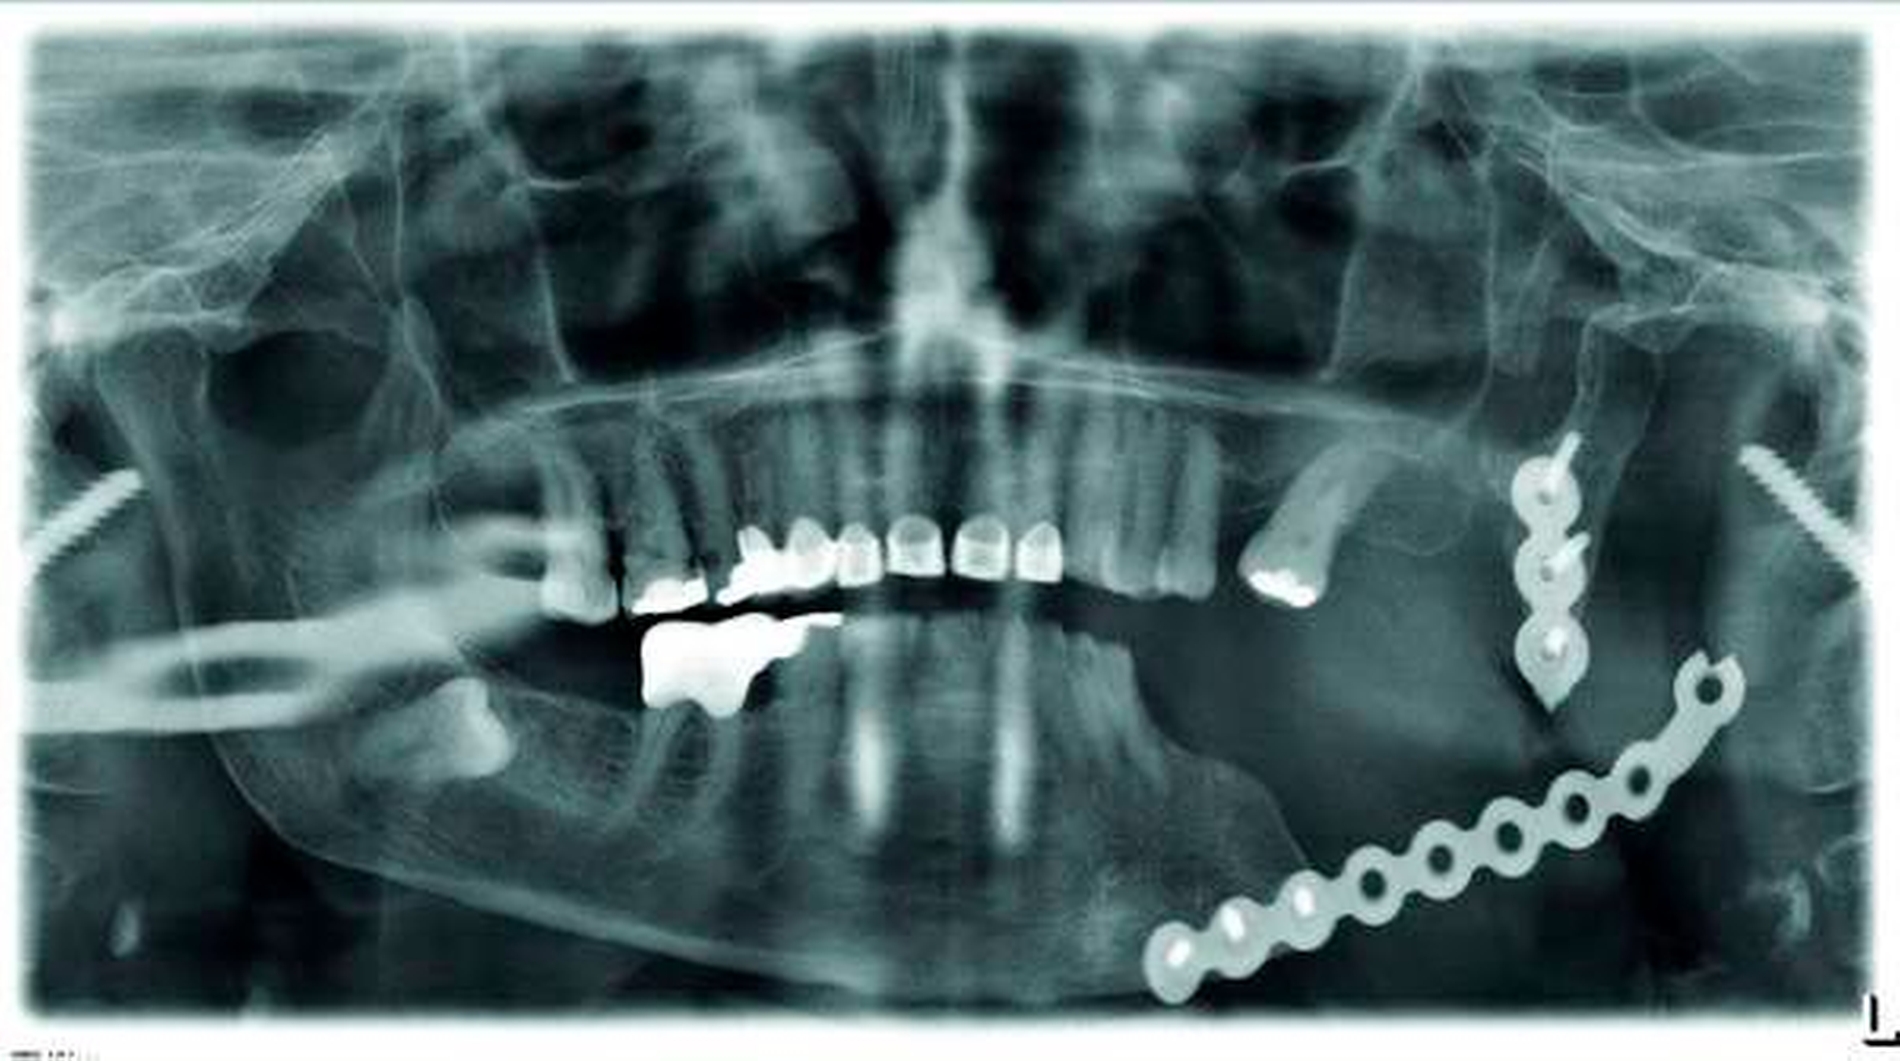

In der Kontrolle mittels Orthopantomogramm (OPG) zeigte sich dann die Fraktur der Rekonstruktionsplatte (Abbildung 1). Das proximale Fragment mit Kondylus war in seiner Dimension zu gering, um eine erneute belastungsstabile Osteosynthese durchführen zu können. Als Option stand hier die TEP zur Verfügung. Für die ossäre Mandibularekonstruktion entschieden wir uns, gleichzeitig ein zweiteiliges Fibulatransplantat als composite graft zu transplantieren.

Abbildung 2 zeigt in der CT die Ausgangssituation mit frakturierter Rekonstruktionsplatte und massiver Okklusionsstörung durch die Innenrotation der Mandibula.

Das postoperative OPG (Abbildung 10) zeigt die Übereinstimmung von Planung und Realität. Die Fossakomponente ist in der röntgenologischen Bildgebung nicht sichtbar, da das verwendete Material aufgrund der Biokompatibilität und Abriebsfestigkeit nicht röntgenopak ist.

Abbildung 14 zeigt das postoperative OPG. Durch die optimale Planung konnte die Kollision von Implantaten, PSI und Fixationsschrauben vermieden werden, was somit die Implantation erst möglich machte.